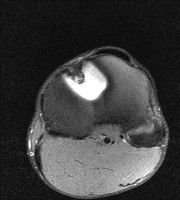

무릎 mri 간단히 봐주실 수 있으시나요 ㅠㅠ

안녕하세요 8년전 십자인대 수술하고 최근 무리한 운동에 무릎 불편감이 생겨서

mri 찍었습니다.

진단결과는 첫 찍은 병원에서 활액막염 이라는 진단을 받았습니다. 혹시 봐주실 수 있으실까요?

올라온 MRI가 단편적이라서 정확한 진단에 어려움이 있지만 십자인대에는 큰 이상이 있지는 않은것 같으며, 무릎관절내 물이 있는 것으로 보아 활액막염의 진단이 맞을 것 같습니다.

하지만 단편적인 영상이기 때문에 촬영병원에서 정확한 판독지 등을 받으시는 것이 좋겠습니다.